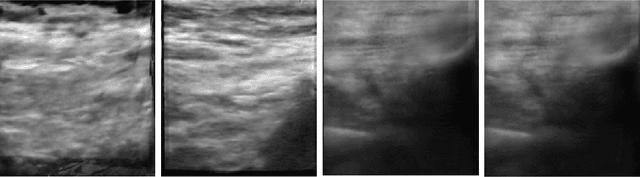

Abstract:Current methods for performing 3D reconstruction and novel view synthesis (NVS) in ultrasound imaging data often face severe artifacts when training NeRF-based approaches. The artifacts produced by current approaches differ from NeRF floaters in general scenes because of the unique nature of ultrasound capture. Furthermore, existing models fail to produce reasonable 3D reconstructions when ultrasound data is captured or obtained casually in uncontrolled environments, which is common in clinical settings. Consequently, existing reconstruction and NVS methods struggle to handle ultrasound motion, fail to capture intricate details, and cannot model transparent and reflective surfaces. In this work, we introduced NeRF-US, which incorporates 3D-geometry guidance for border probability and scattering density into NeRF training, while also utilizing ultrasound-specific rendering over traditional volume rendering. These 3D priors are learned through a diffusion model. Through experiments conducted on our new "Ultrasound in the Wild" dataset, we observed accurate, clinically plausible, artifact-free reconstructions.